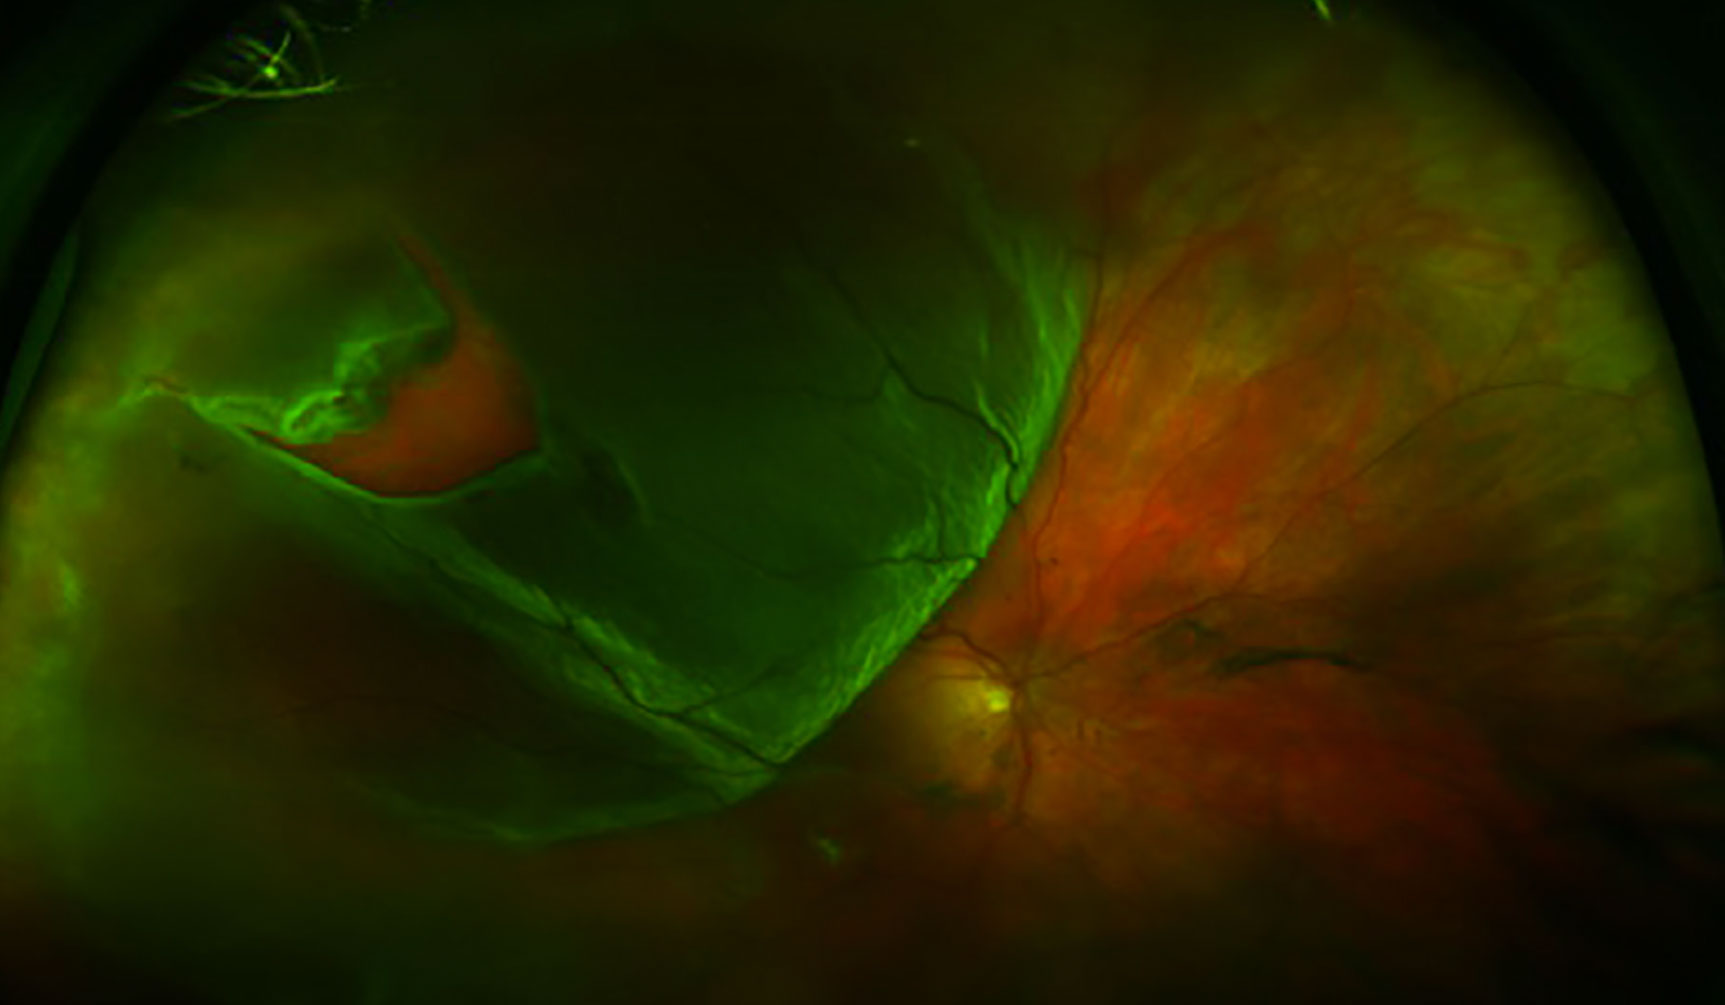

열공망막박리(RRD)는 **망막열공(retinal break)**을 통해 유리체액이 망막하 공간으로 유입되어 신경감각망막이 RPE에서 분리되는 안과 응급질환입니다. 치료하지 않으면 실명에 이릅니다.

분류 및 증상/징후 (Classification & Signs)

증상

- 비문증 → 광시증 → 시야결손(커튼 치는 듯) → 중심시력 저하(macula off)

분류

- Macula-on: 중심와 비침범 — 24-48시간 내 수술 권고

- Macula-off: 중심와 침범 — 가능한 빨리 (시력 예후 제한적)

진단 (Diagnosis)

- 산동 안저검사: 주변부까지 scleral depression — 열공 위치/수, 박리 범위